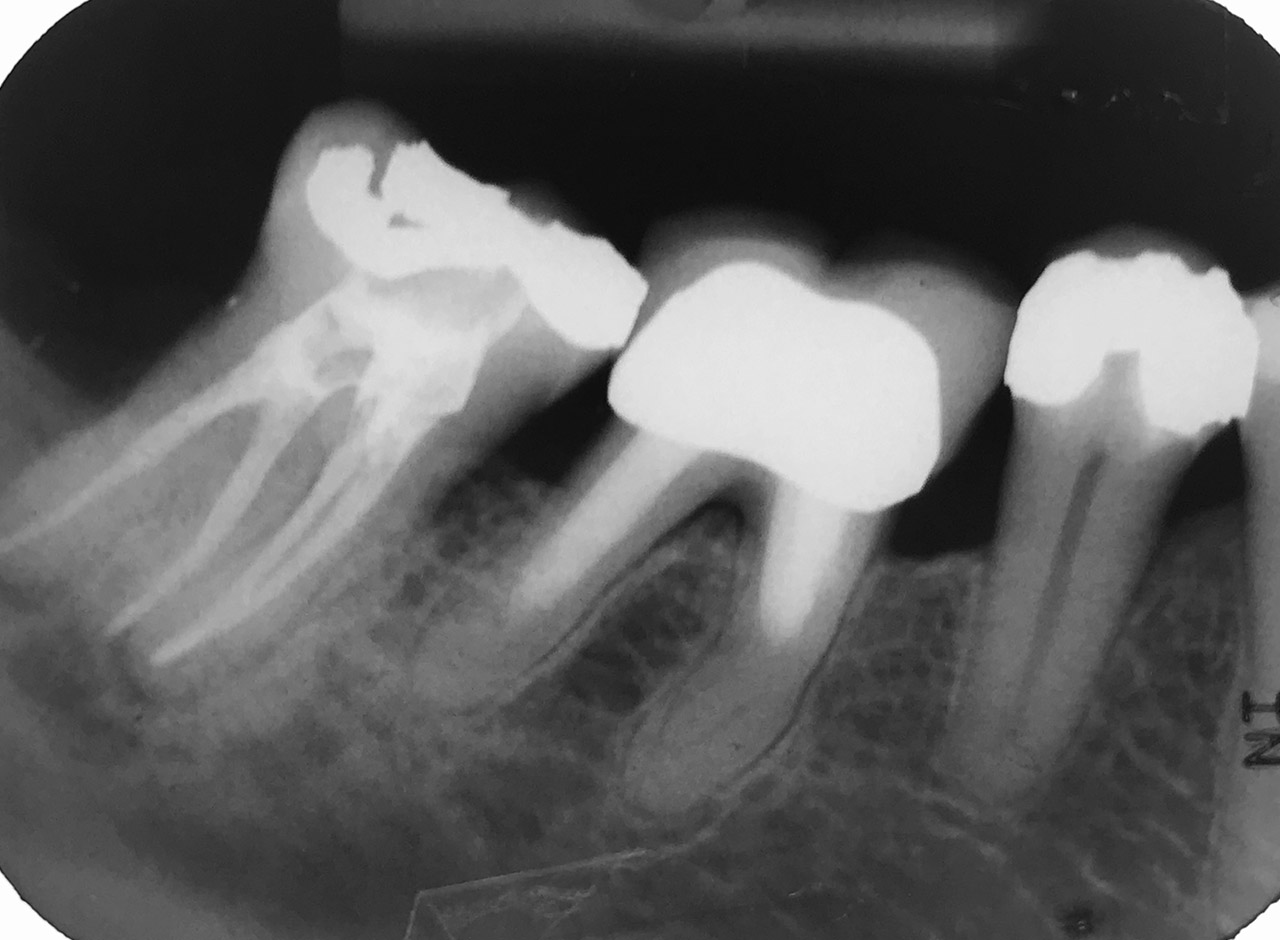

Endodontie/Wurzelbehandlung:

Befund: Aufbißschmerz und Schwellung auf Zahn 46. Frisch zementierte Krone (alio loco).

Therapie: Abnahme der Krone, Entfernung der Zementreste, Revision der insuffizienten Wurzelbehandlung.

Glasfaserstifte und neue Krone, beides adhäsiv zementiert.

Wurzelbehandlung/Endodontie:

Massiver Paro-/Endodefekt bei den Zähnen 38&37. Extraktion von 38 (Weisheitszahn) und Wurzelbehandlung von 37 (4 Kanäle). Defekt vollständig ausgeheilt.